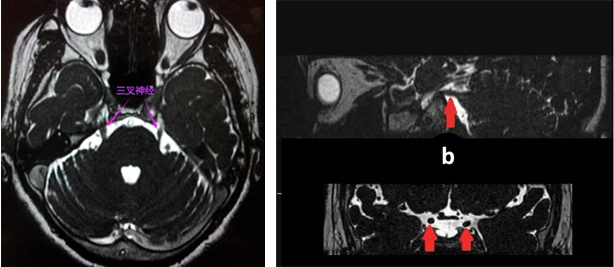

近日,昌宁县中医医院影像科成功开展三叉神经MRI(磁共振成像)检查新技术,为三叉神经痛及相关疾病的精准诊断提供了新的有力工具。该技术能够清晰显示三叉神经的细微解剖结构及其与周围血管的关系,显著提高了诊断的准确性和可靠性。

1.软组织分辨率高:能够清晰地分辨出三叉神经与周围的血管、脑组织等结构的界限。例如:在检查三叉神经痛是否由血管压迫引起时,MRTA可以清晰地看到血管与神经的交叉、压迫情况。

2.多方位成像:可以多角度观察三叉神经,全面了解其形态和走形,有助于确定肿瘤的范围、与神经的关系等。